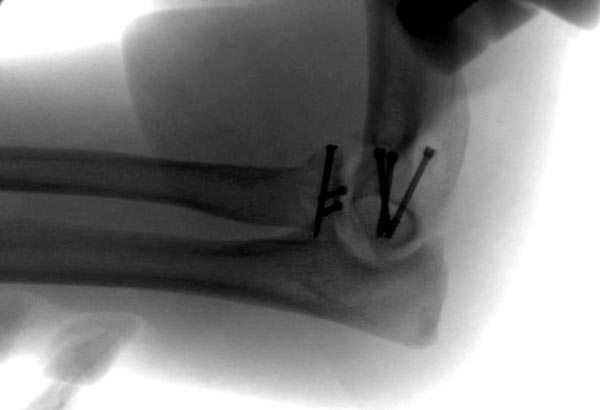

Re: ПЕРЕЛОМ ГОЛОВКИ ЛУЧЕВОЙ КОСТИ.